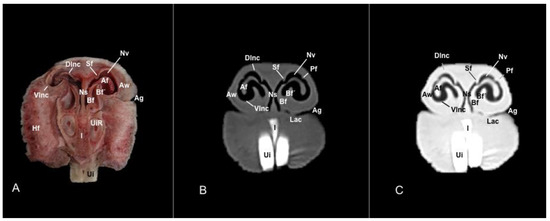

3.1. Anatomical Sections

3.2. Computed Tomography (CT)